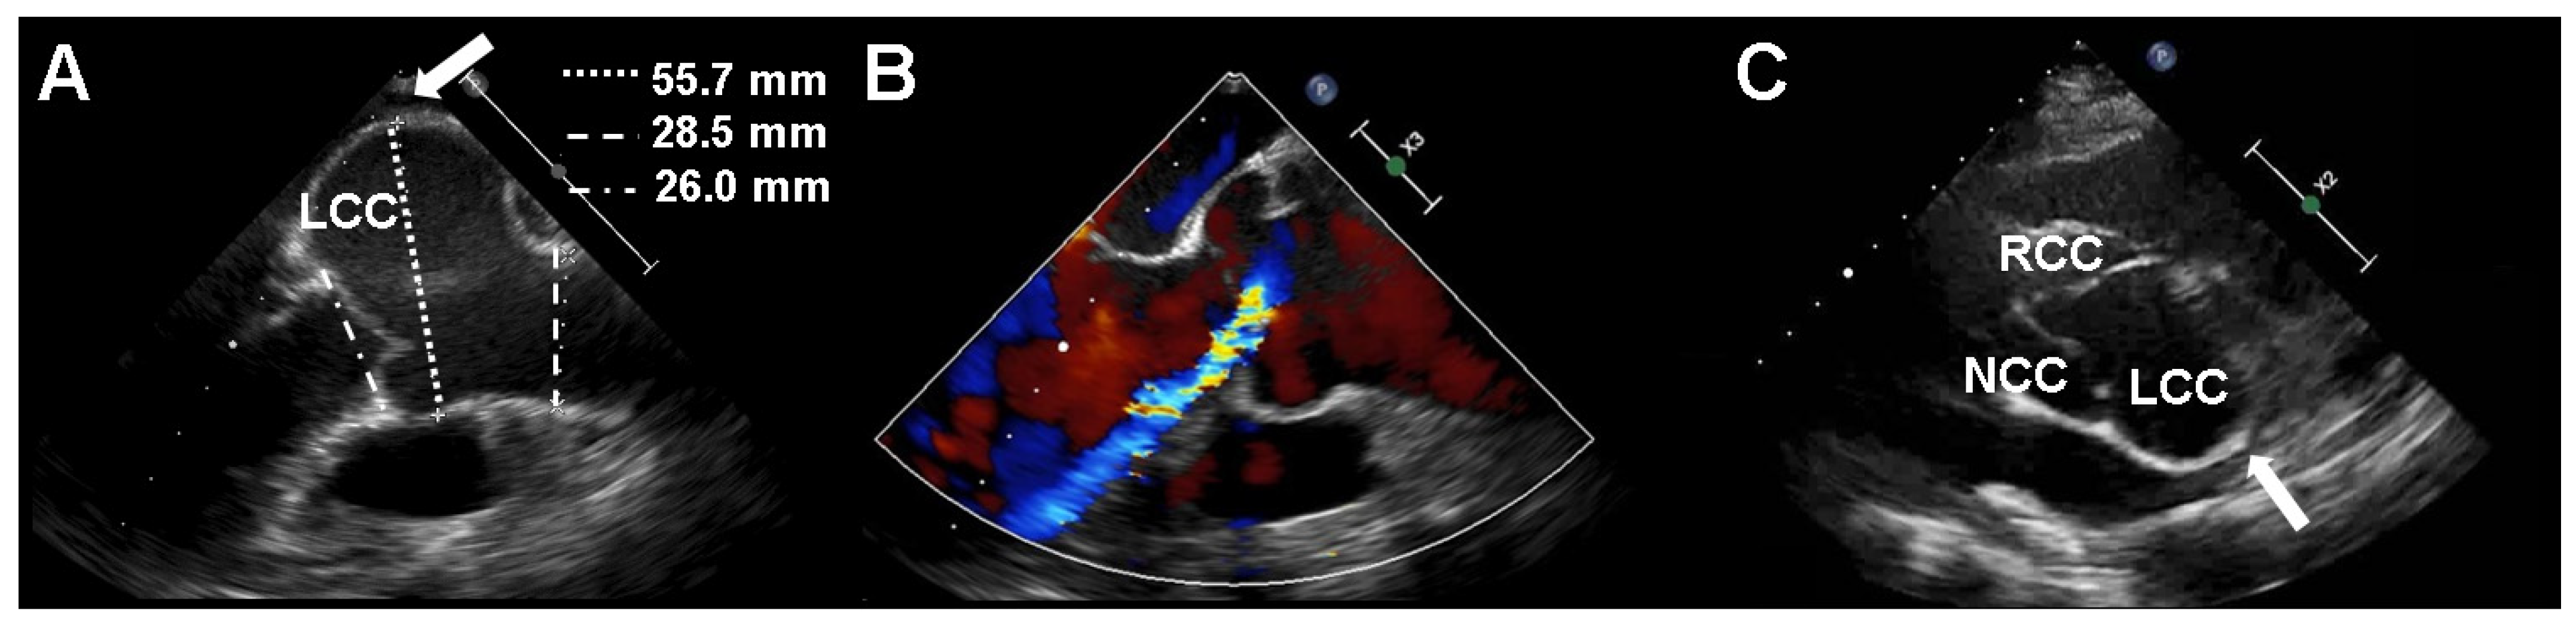

2. Case Presentation